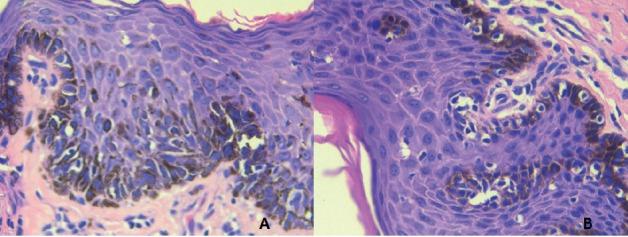

Melanoma of the urogenital tract is extremely rare, accounting for less than 0.1% of melanoma cases. The global literature currently describes only 220 cases of penile melanoma, most commonly located on the glans penis.

Penile melanoma accounts for 0.7% of penile cancers and 0.18% of melanoma cases. The average patient age for the six cases we reviewed was 44.5 years. Three of these cases (50%) involved ulceration, one case (16.7%) involved lymphovascular invasion, and three cases (50%) involved mitosis ≥ 1 mm (0.38-4.7 mm). The average depth of invasion (Breslow) in the five cases that reported this measure was 2.1 mm (0.38-4.7 mm). Applying the American Joint Committee on Cancer tumour, node, metastases (AJCC TNM) staging system, one case was Tx (16.7%), two cases were T1 (33.3%), one case was T2 (16.7%), one case was T3 (16.7%), and one case was T4 (16.7%). Five cases (83.3%) involved wide local resection, and only one case involved partial penile amputation. Four cases (66.7%) involved primary bilateral inguinocrural lymphadenectomy, and only one of those four cases involved lymphatic metastatic disease. One case (16.7%) involved lymphatic recurrence at 12 months in a patient who survived 38 months. One case (16.7%) involved local recurrence at 13 months in a patient who has survived 53 months. Eighty per cent of these patients remain alive, with no evidence of disease after an average follow-up of 96.7 months.

Penile melanoma prognosis depends on the initial clinical stage of the disease. The risk of lymphatic involvement seems to be related to the same risk factors used to assess cutaneous melanoma. Clinicians can thus assess penile melanoma using the AJCC staging system. The use of sentinel lymph node biopsy to determine staging is also becoming more common and could replace prophylactic bilateral inguinal dissection.